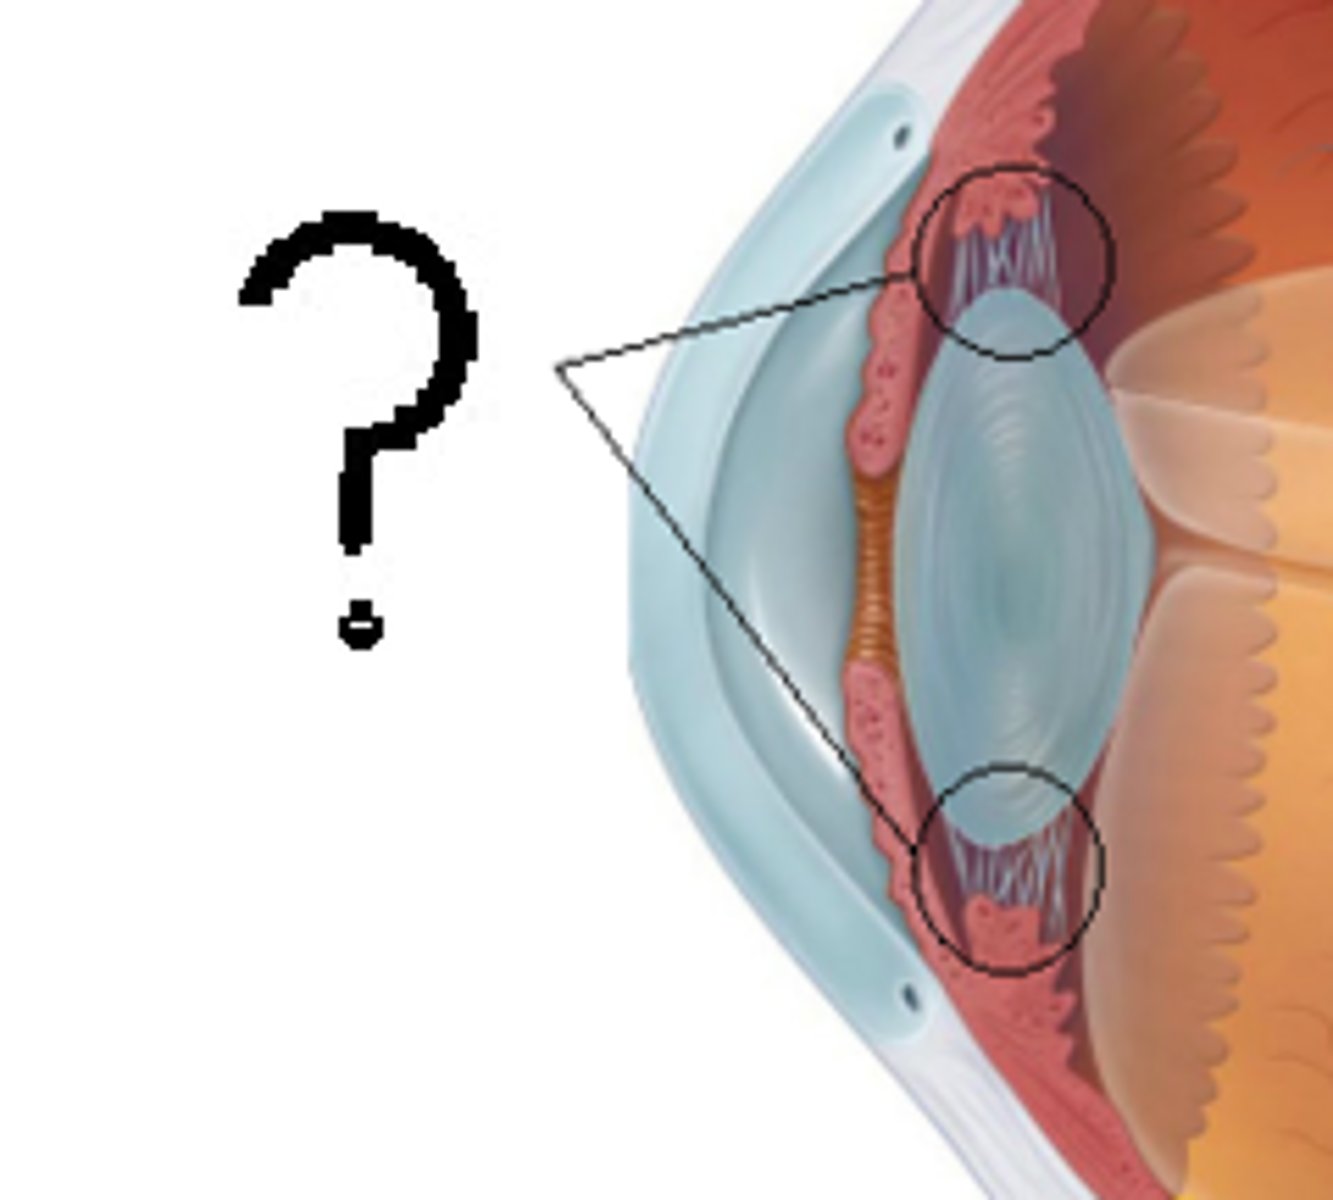

anterior cavity (of eye)

iris

B

ciliary body

B

ciliary process

suspensory ligaments

C

lens

F